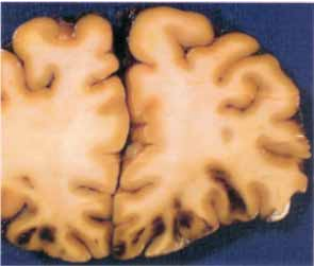

79 一名有酒精性肝病的成年男性,離開卡拉 OK 店不久,被發現倒於路邊,送醫不治死亡,解剖所見 如圖示。這病變應是: (A)對側性腦挫傷 (B)高血壓性腦出血 (C)硬膜下出血 (D)腦梗塞